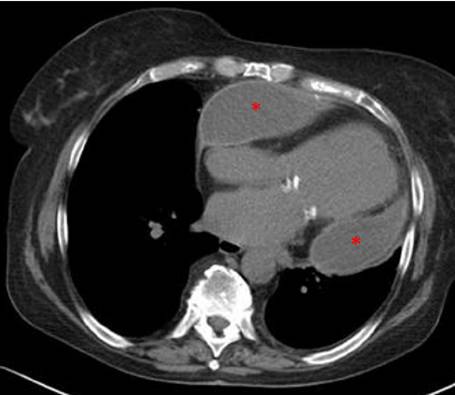

lCT或CMR:包裹性心包积液,心包增厚和肿物,胸部疾病

lCT和/或CMR:为二线检查,显示心包钙化(CT),增厚,心包受累程度、范围。